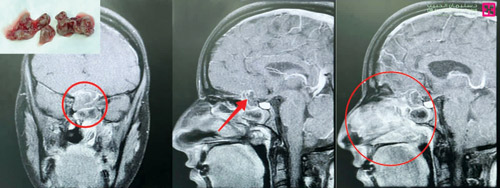

ذكر ذلك الدكتور هاني الجهني استشاري جراحة المخ والأعصاب والعمود الفقري الحاصل على البورد الفرنسي رئيس الفريق الطبي المعالج، والذي أضاف أنه فور وصول المريضة للعيادة تم إخضاعها للكشف السريري وإجراء عددٍ من الفحوصات الدقيقة المخبرية وعمل التصوير المقطعي (C.T Scan) والرنين المغناطيسي (M.R.I)، وقد أثبتت النتائج وجود ورم فطري من النوع النادر جداً، بطول 6 سم ومتمركز في الجيوب الأنفية ومتمدد داخل تجاويف الجيوب الأنفية وصولاً لقاع الدماغ، ومسبباً تآكل العظام الفاصلة بين الجيوب الأنفية والمخ.

مشيراً إلى أنه تم تجهيز المريضة للعملية مع إعطائها مضادات حيوية، وقد استغرقت الجراحة تحت التخدير العام 3 ساعات باستخدام تقنيات المنظار المتطور، حيث تم فك الالتصاقات وتحرير الورم من تشعباتها داخل تجاويف الجيوب الأنفية، وإجراء عملية تنظيف كاملة لتلك المنطقة، وذلك للقضاء على الفطريات، ومن ثم إجراء ترميم للمنطقة العظمية المتآكلة من خلال أخذ غشاء من أنسجة الفخذ وإجراء ترقيع عظمي، وذلك للحيلولة دون خروج سوائل المخ ومنعها من التسرب.